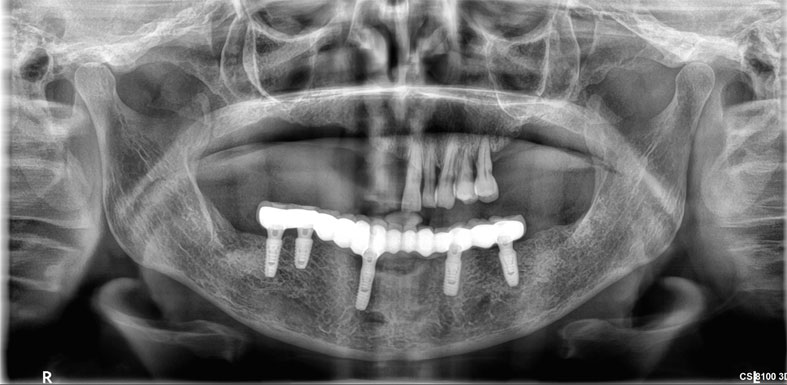

Dental implants are artificial tooth roots use to replace decayed or missing teeth. They are a popular and effective long-term solution, dental implants are placed into the jawbone, providing a stability for replacement teeth.